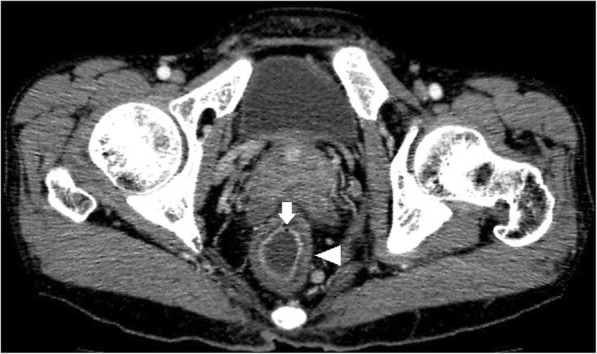

Fig. 1.

Axial CTE of UC showed uniform mural thickening and stratification in rectum (arrowheads). Mucosal hyperenhancement and mucosal bubbles (arrows) sign were detected

Of the total 46 cases, bowel wall thickening was seen in 43 cases (Figs. 1, 2, 3, 4). Mural hyperenhancement was observed in 45 cases (Figs. 1, 2, 3, 4). Mural stratification was present in 21 cases (Figs. 1, 2, 4). Mucosal bubbles were present in 30 cases (Fig. 1). Loss of haustration was identified in 28 cases (Fig. 3). Mesenteric hyperemia was present in 23 cases (Figs. 2, 3, 4). Perirectal stranding was seen in 14 cases (Fig. 2). Lymph node enlargement was present in 19 cases. Intestinal pseudopolyps were identified in five patients (Fig. 4). Luminal narrowing was seen in 12 cases (Fig. 3).